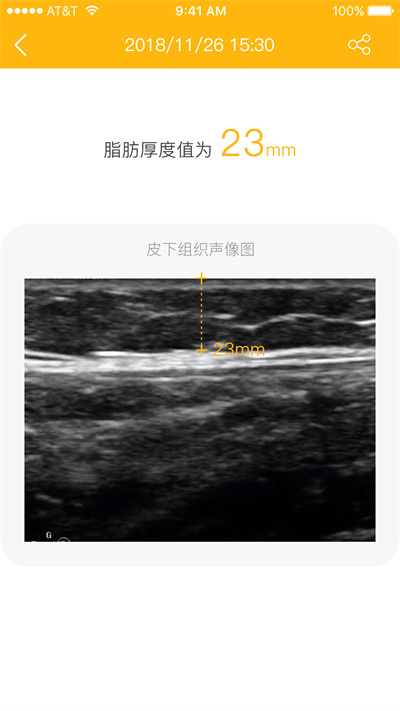

【操作简单,2s出结果】

置于测量处,按下按键,2s输出脂肪厚度数值;测量过程无需复杂设置,老人小孩都能轻松上手。应用还提供语音播报功能,测量结果会自动朗读,方便视力不佳的用户使用。测量数据会自动保存云端,换设备也能查看历史记录。